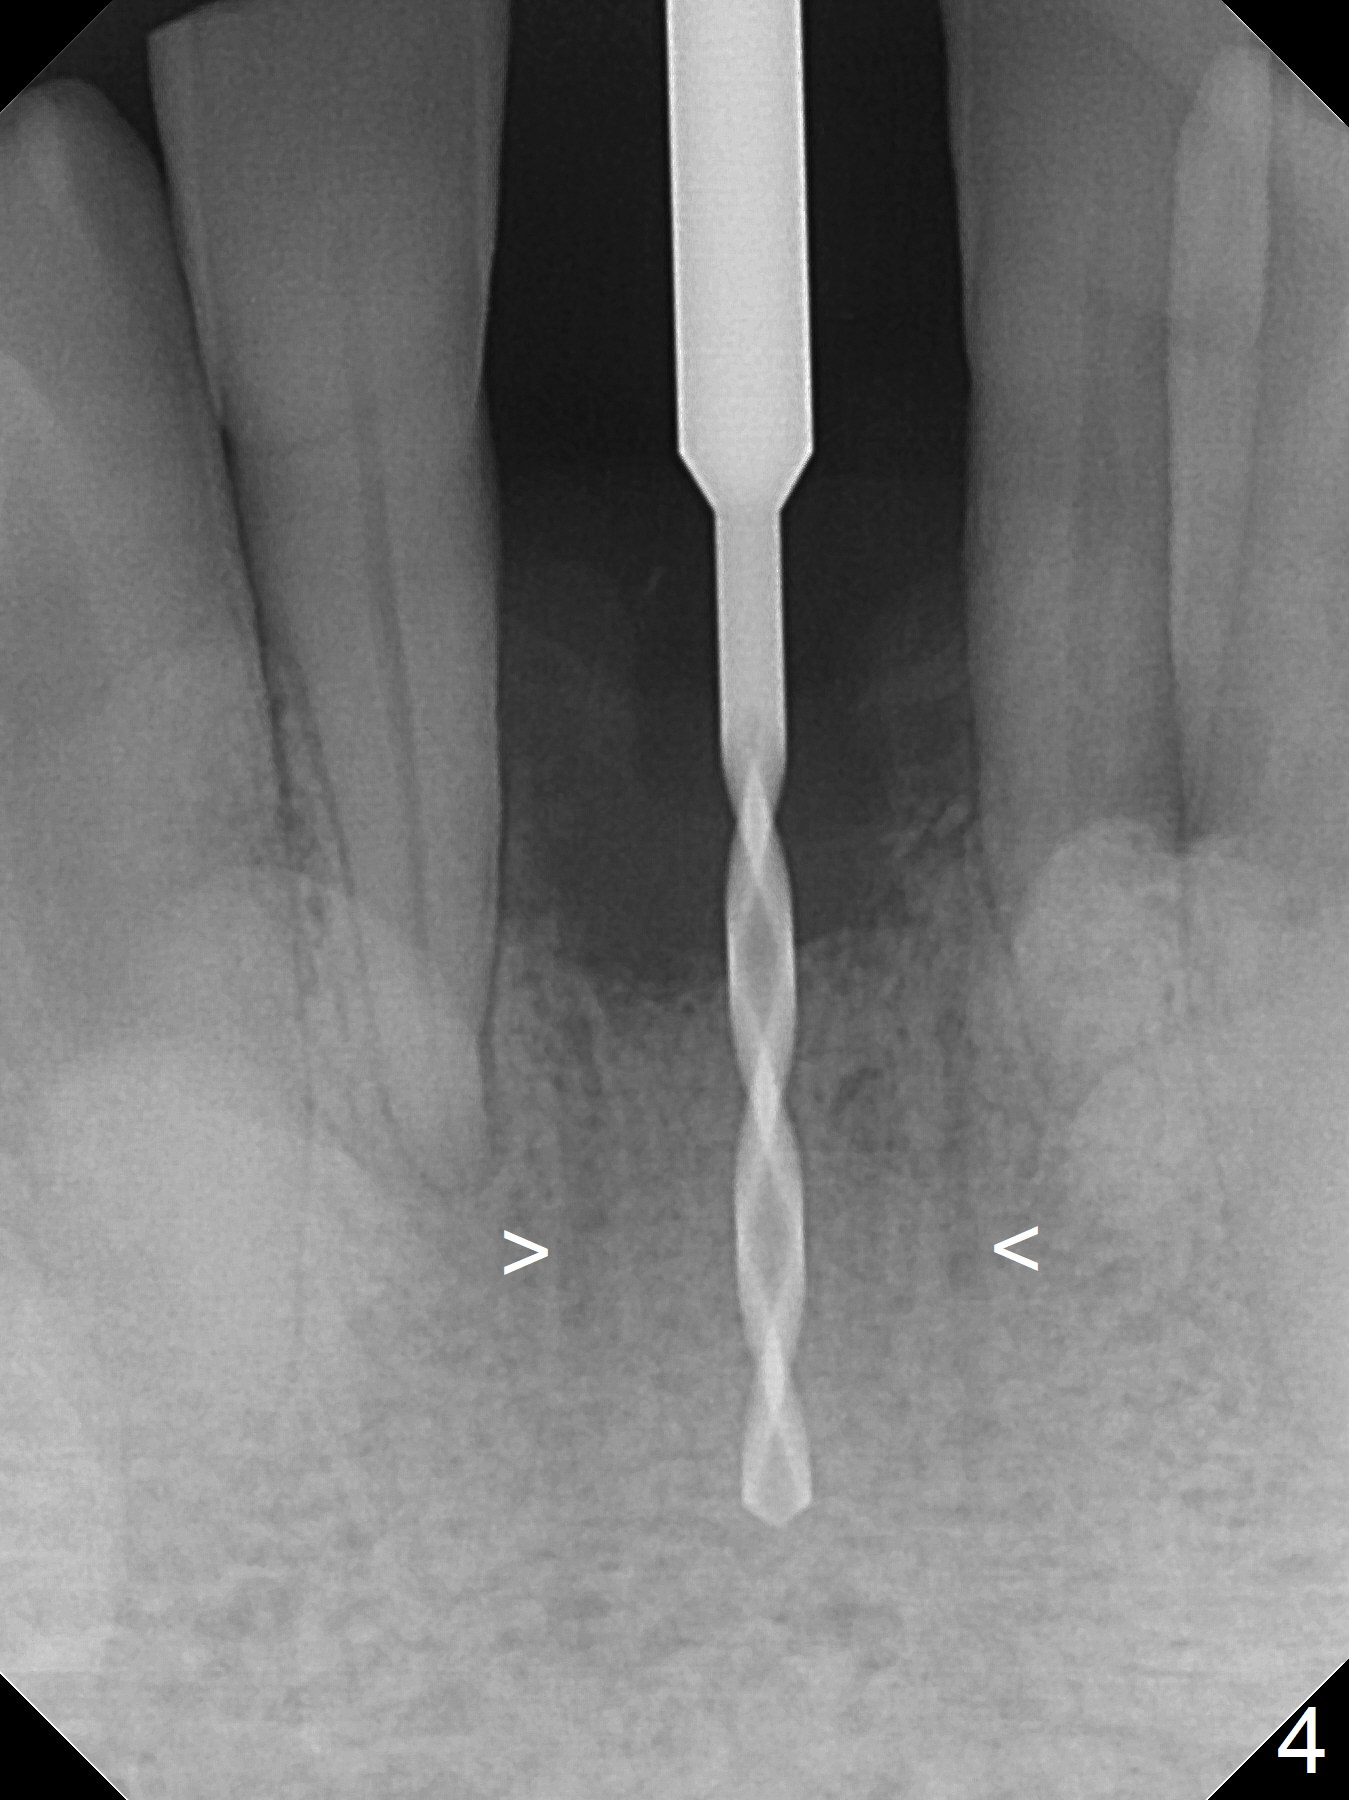

When the patient returns for implant placement 1.5 years after the last treatment (SRP), the tooth #25 has exfoliated, whereas the tooth #24 is severely displaced (Fig.1-3). In fact the buccolingual plates are found to be lost after extraction, corresponding to change in gingival color indicated by an arrowhead in Fig.1. Initial osteotomy with 1.2 mm drill is parallel to the terminal branches of the Incisive Canal (Fig.4 arrowheads). Since the gingiva is as thick as 7.5 mm (Fig.3 arrow), a 3x14 mm 1-piece implant with 4 mm cuff is placed (Fig.5); three implant threads are outside the native bone; with allograft (*) placed and the neighboring crests being coronal to the threads, the chance of periimplantitis should be remote. An immediate provisional is fabricated to contain the graft in place. Meanwhile the tooth #2 is symptomatic with crack. The top 3 threads appear to be contacted by the newly formed crestal bone 6 months postop (Fig.6 *). Bone appears to have grown into the space between implant threads 6 months post cementation (13 months postop).